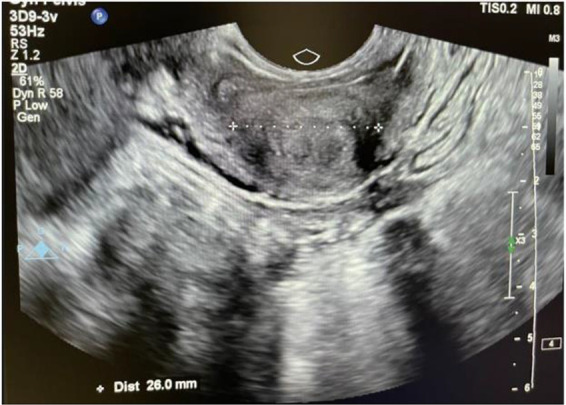

Methods: In this case-control study, the case group consisted of nulliparous women with endometriosis, while the control group comprised nulliparous women without endometriosis. A total of 42 individuals were included in each group. Cervical length was measured using transvaginal ultrasound from the external os to the internal os. The patients in the case group underwent laparoscopy to confirm the diagnosis. Pearson chi-square test and Fisher's exact test were employed to compare categorical variables with a p<0.05 considered statistically significant.

Results: In both groups, there were no notable variations in any of the demographic characteristics. However, the severity of dysmenorrhea was significantly different between the two groups (p=0.01). The average diameter of the mediolateral cervix (29.48±6.2 and 27.14±3.8) was statistically significant between the patient group and control group, respectively (p=0.04). The mediolateral width may have a positive predictive effect on the presence of endometriosis, while cervical length appears to have a protective effect against endometriosis.

Conclusion: Demographic data do not predict endometriosis. This study suggests that mediolateral width in transvaginal sonography can serve as a minimally invasive diagnostic tool for endometriosis, showing correlation with endometriosis symptoms like dysmenorrhea and dyspareunia.